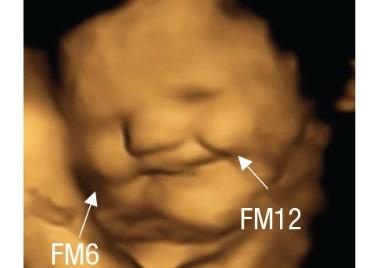

A team of scientists studied 4D ultrasound scans of 100 pregnant women and discovered that babies exposed to carrot flavors showed "laughter-face" responses.

Those exposed to kale flavors, in contrast, showed more "cry-face" responses.